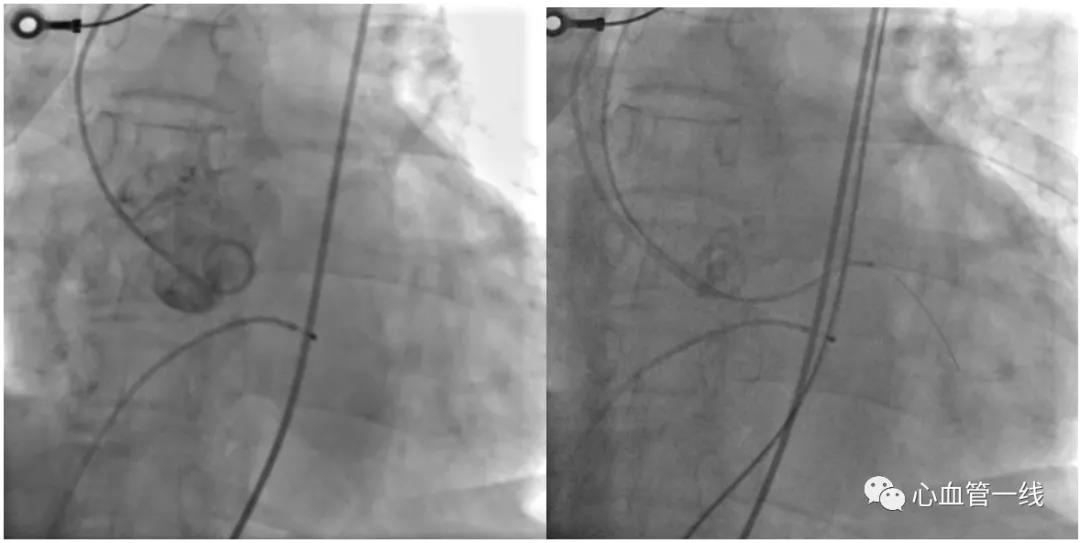

充分药物治疗后,行冠脉造影检查如下所示:

造影显示前降支中段局限性狭窄约60%,第一对角支开口狭窄约80%,右冠中段扭曲处高度狭窄约95%。